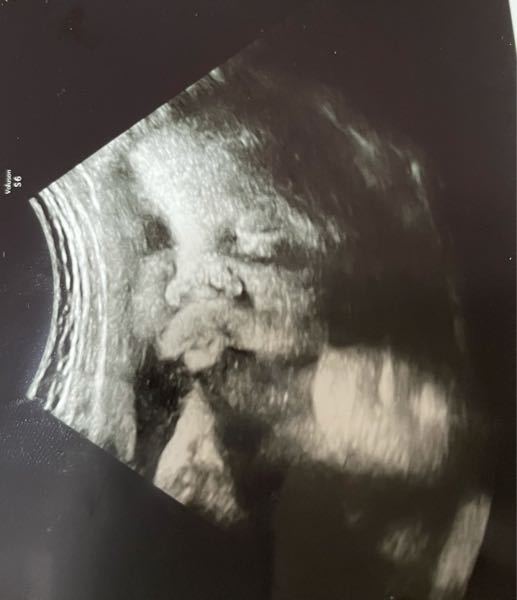

胎児しゃっくり運動 超音波動画 Youtube